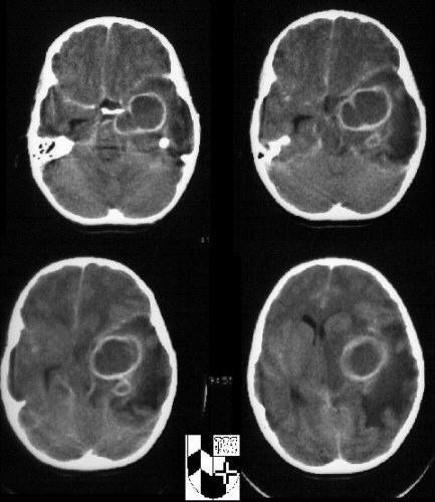

what can hydrocephalus on the CT look like

dilated ventricles

what is this aqueductal stenosis causing

hydrocephalus on MRI

what space would be more dilated: space after aqueductal stenosis or before it

before